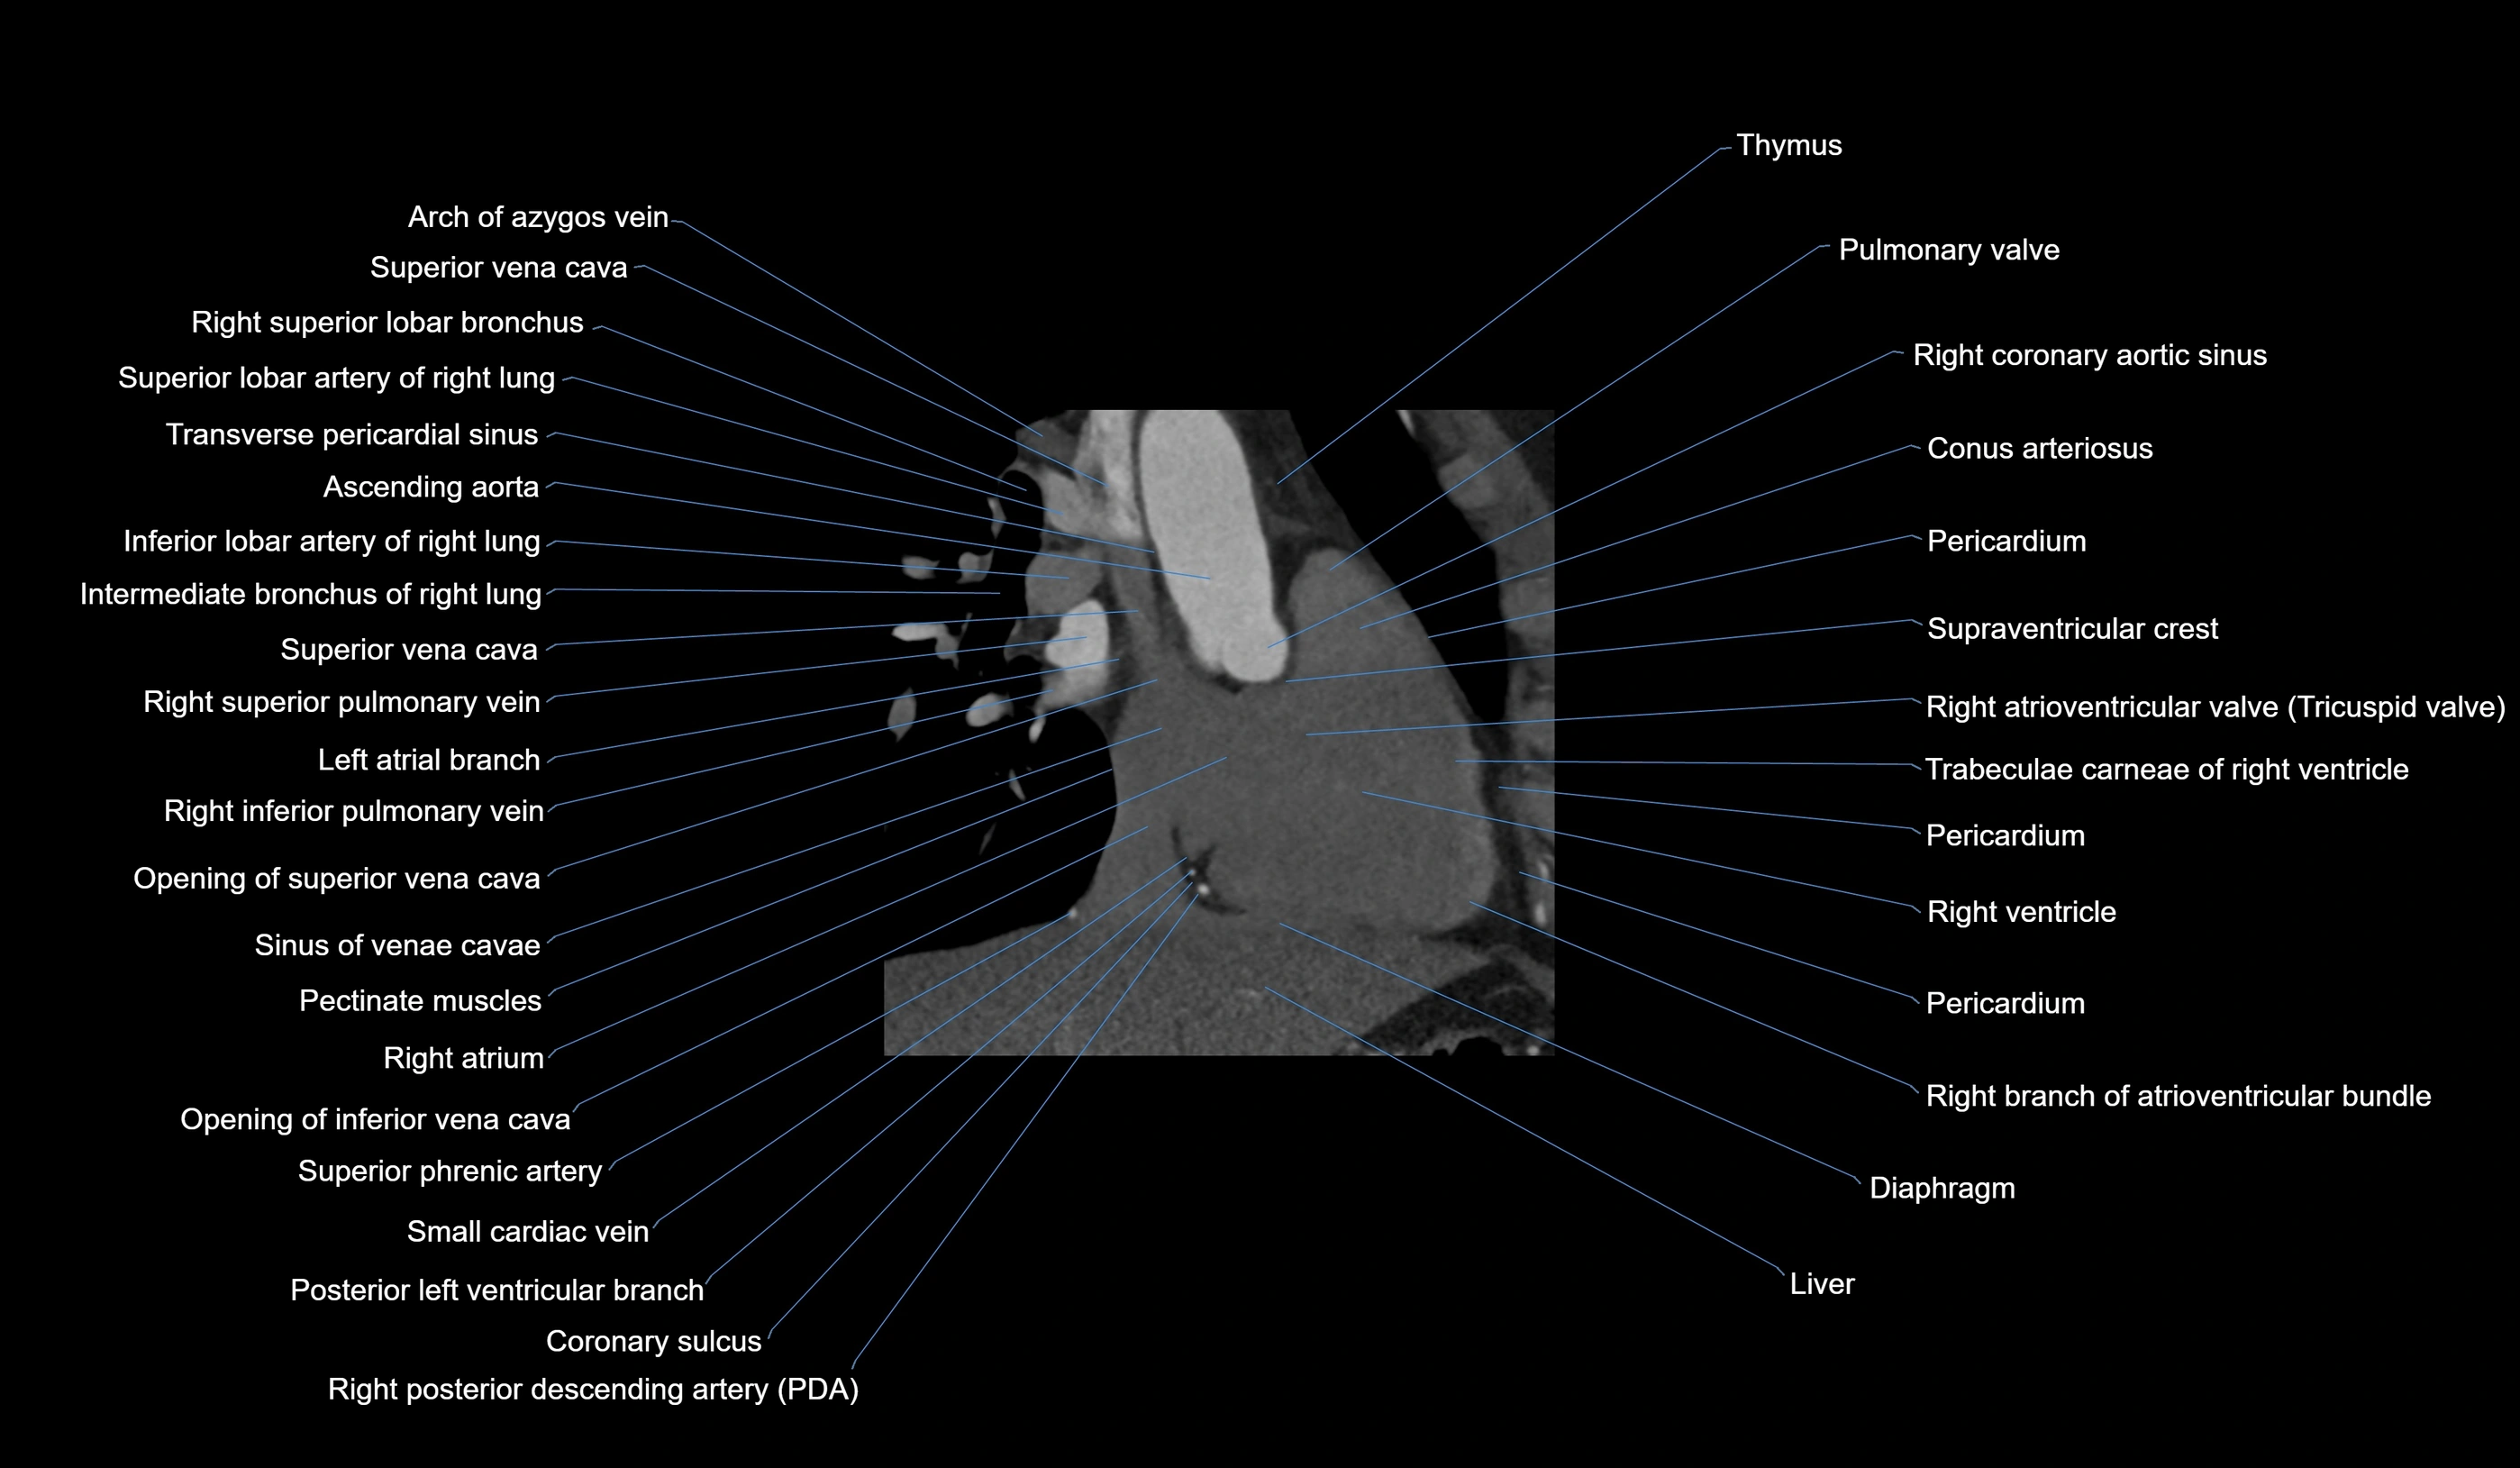

- Right atrium

- Right ventricle

- Right atrioventricular valve (tricuspid valve)

- Right branch of atrioventricular bundle

- Right coronary aortic sinus

- Conus arteriosus

- Pulmonary valve

- Superior vena cava

- Right posterior descending coronary artery (Right PDA)

- Sinus of venae cavae (sinus venarum)

- Pectinate muscles

- Opening of superior vena cava

- Opening of inferior vena cava

- Small cardiac vein

- Superior lobar artery of right lung

- Right superior lobar bronchus

- Right intermediate bronchus

- Right superior pulmonary vein

- Right inferior pulmonary vein

- Left atrial branch (coronary artery)

- Superior tracheobronchial lymph nodes

- Diaphragm

- Heart